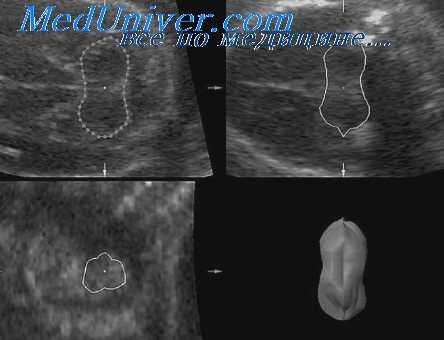

Воротниковым пространством (ВП) называется скопление жидкости в области задних отделов шеи плода человека, которое обычно визуализируется при ультразвуковом исследовании после 9 нед беременности по менструальному сроку. Измерение толщины ВП можно проводить в сроки от 10-й до 14-й нед гестации у плодов с величиной копчико-теменного размера (КТР) от 38 до 84 мм. Увеличение толщины ВП сопровождается повышенным риском наличия хромосомных аберраций (особенно трисомии 21), а также других нехромосомных аномалий и синдромов, о которых пойдет речь ниже.

Чаще всего воротниковое пространство можно наблюдать в сроки беременности от 10 до 14 нед, потому что в этот период лимфатическая система продолжает развиваться, а сосудистое сопротивление периферического русла плаценты еще сохраняется достаточно высоким. После 14 нед резистентность плацентарного бассейна снижается, а лимфатическая система становится достаточно развита для того, чтобы дренировать скопившееся количество жидкости.

Измерение толщины воротникового пространства не представляет сложности. Для того чтобы точно определить вероятность Риска, необходимо при его оценке соблюдать следующие принципы:

• измерения можно выполнять как при помощи трансвагинального, так и трансабдоминального доступа, при этом необходимым условием является возможность получения продольной (сагиттальной) плоскости сканирования плода;

• изображение нужно увеличить так, чтобы плод занимал не менее 75% площади изображения на экране монитора;

• для измерения максимальной толщины ВП маркеры курсора должны быть установлены на внутренней поверхности кожи и наружной поверхности мягких тканей, покрывающих шейный отдел позвоночника;

• если плод лежит на спине близко к амниотической оболочке, необходимо подождать эпизода его двигательной активности, чтобы убедиться, что пространство между спиной плода и амниотической оболочкой не было ошибочно воспринято за ВП. Из этого графика следует, что толщина ВП увеличивается с увеличением КТР и соответственно с увеличением срока гестации. Медиана и 95-й процентиль толщины ВП при величине КТР 38 мм составляют 1,3 мм и 2,2 мм, а при КТР 84 мм - 1,9 мм и 2,8 мм соответственно. Толщина ВП менее 2,5 мм считается нормальной (или менее 3 мм при использовании оборудования, которое при измерениях дает округление до миллиметра).